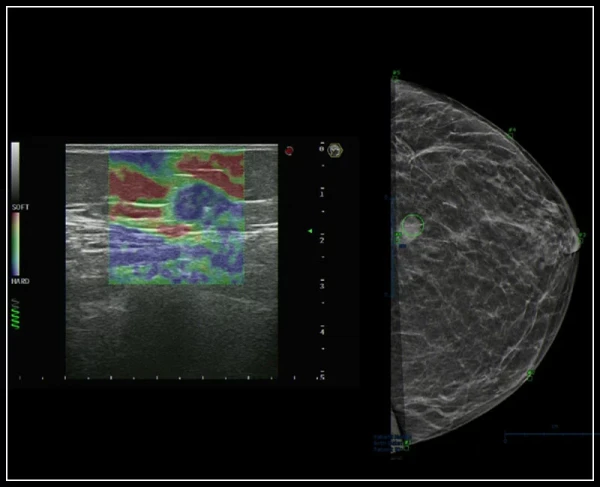

Kesish to'lqinining elastografiyasi: grafik va raqamli shaklda to'qimalarning qattiqligini miqdoriy o'lchovlari

ULTRA-Color Doppler rangli xaritalash usullari: yuqori sezuvchanlik, chuqur kirish va yuqori aniqlik